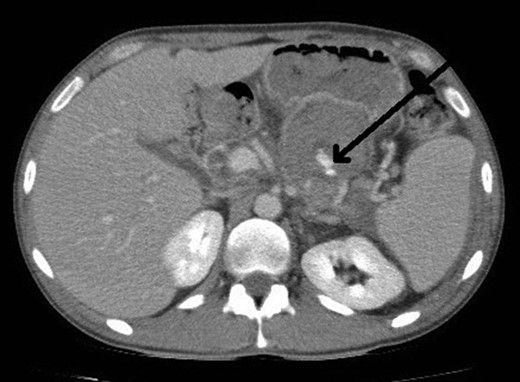

The next step was an endoscopic ultrasound guided thrombin injection. This was carried out and 2 ml of thrombin was injected into the pseudoaneurysm to good effect with no immediate complications. Also, percutaneous drainage of the perisplenic collection was carried out, where 400 ml of pus was drained. A follow-up duplex ultrasound scan confirmed that there was no flow in the pseudoaneurysm (Fig. 3).

Ultrasound image demonstrates the thrombosed pseudoaneurysm 24 h post thrombin injection.